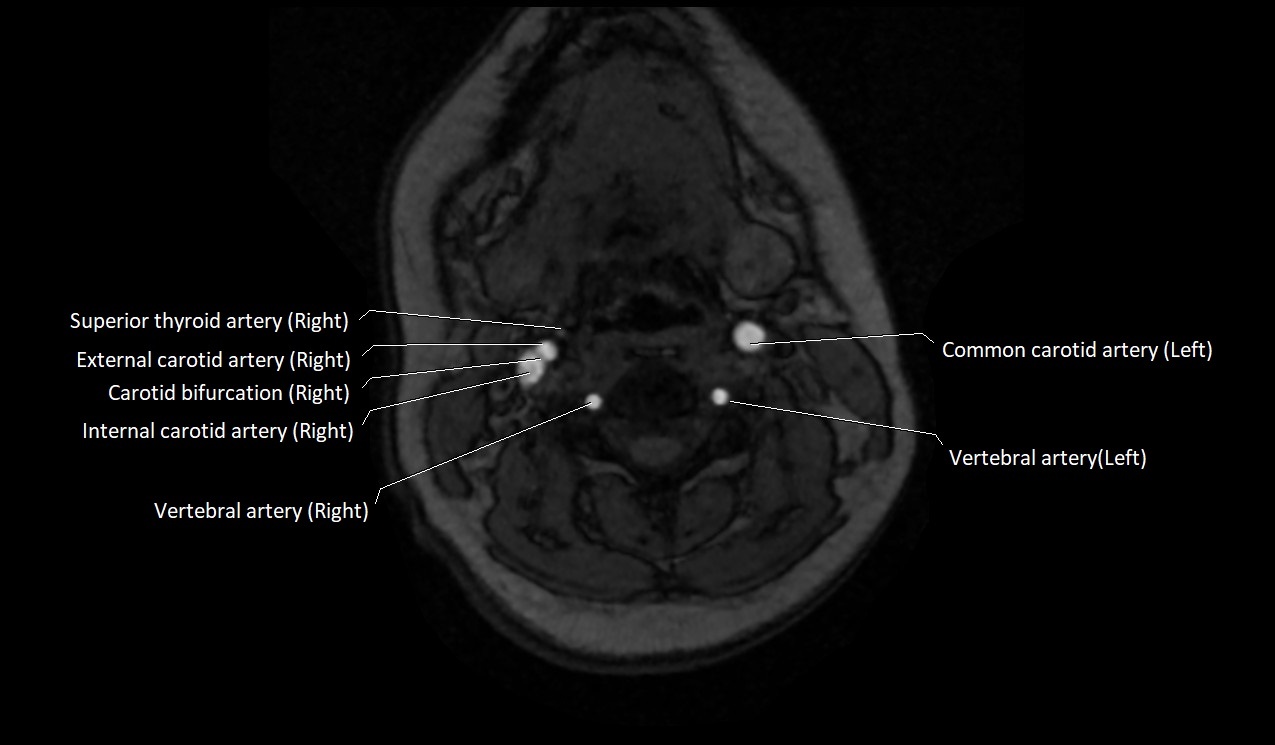

MRI images

image